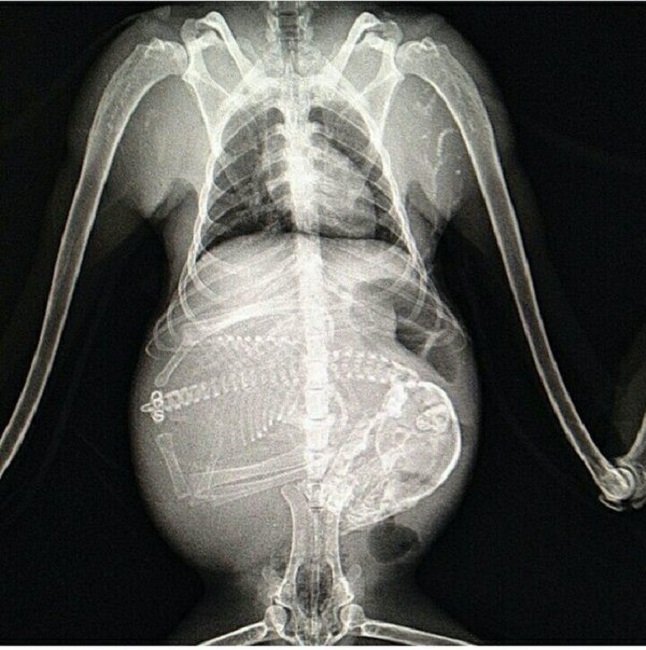

You might have seen many turtle eggs laid out in the beach, sometimes hidden by sand. Did you know that mother turtles rush to the beach to lay their eggs, usually to the same beach where they were born.

Image Source: tumblr.com